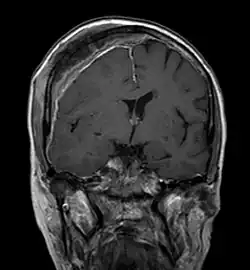

Imagerie par résonance magnétique

Avec l'IRM, on peut en particulier obtenir de bonnes images des tissus mous. C'est un processus idéal pour le diagnostic des métastases spinales (métastases des vertèbres). Avec l'IRM, on peut en outre rendre visible des complications supplémentaires dans la région des métastases spinales, comme des infections ou des blessures des tendons et ligaments, des œdèmes de la moelle osseuse après une fracture récente[120],[121], ou la compression de structures nerveuses[18]p. 16. Au moyen de séquences STIR, il est possible d'évaluer l'âge d'une fracture. Pour la détection des métastases, la pondération T1 avec des produits de contraste au gadolinium, comme l'acide gadotérique est particulièrement bien adaptée. Le produit de contraste s'accumule particulièrement fort dans les métastases[18],[122].

Pour le diagnostic des récidives (2), l'IRM est plus adapté que le scanner. Par exemple, les implants de titane font moins d'artefacts pour l’IRM[87],[123].

- Comparaison scanner/IRM pour des métastases ostéolytique d'un cancer du sein dans la colonne vertébrale

Scanner sagittal reconstruit, représentation dans la fenêtre osseuse. Comme la patiente avait des métastases dans toutes les régions du corps, elle ne pouvait pas lever les bras pour l'examen, ce pourquoi les mains sont présentées.

Scanner sagittale, parties molles. Outre les métastases dans la colonne vertébrale, qui envahissent en partie le canal médullaire vers l'arrière, métastases aussi dans le sternum. Plus des métastases dans le foie.

IRM natif avec pondération T1.

IRM sagittal natif avec pondération T1. On voit clairement l’extension jusqu'aux lames vertébrales.